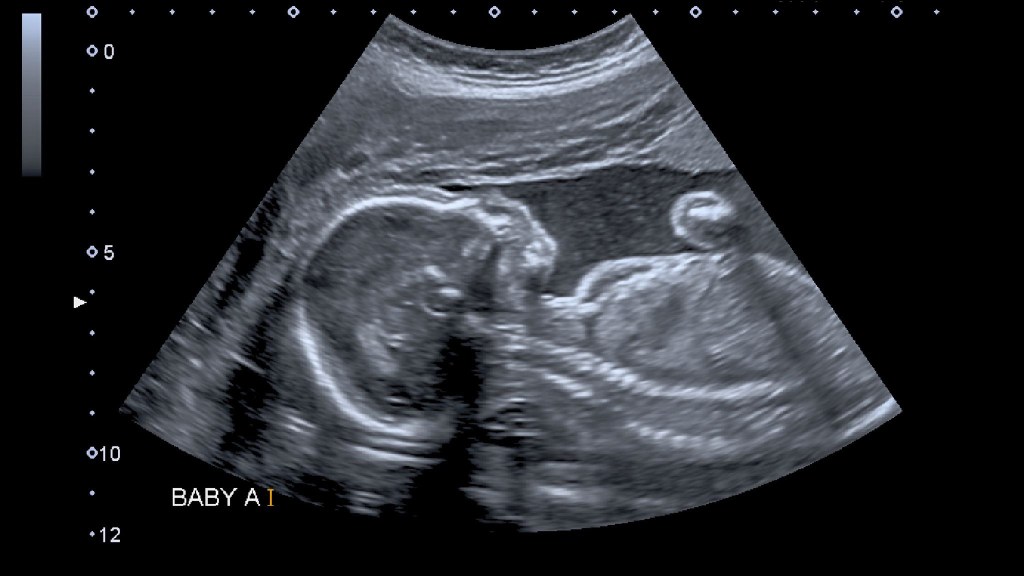

13 For you formed my inward parts;

you knitted me together in my mother’s womb.

14 I praise you, for I am fearfully and wonderfully made.

Wonderful are your works; my soul knows it very well.

We live in a society that very callously talks about the issue of abortion and acts as if we are not discussing the life of unborn babies. Every single one of us is known by God and and every single one of us were knitted together in the womb of our mothers.